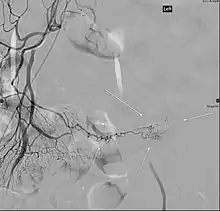

Patients with these misplaced gastric cells may experience peptic ulcers as a consequence. Therefore, other tests such as colonoscopy and screenings for bleeding disorders should be performed, and angiography can assist in determining the location and severity of bleeding. Colonoscopy might be helpful to rule out other sources of bleeding but it is not used as an identification tool.

Angiography might identify brisk bleeding in patients with Meckel's diverticulum.[17]